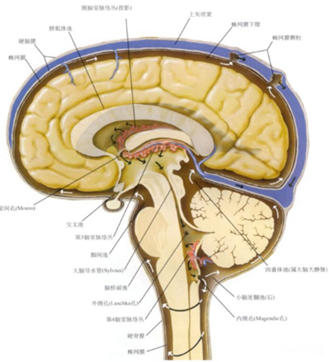

熟悉颅内解剖结构,特别是脑室系统的解剖特征,了解相关的邻近解剖结构以及手术中需要避开的关键区域。

①解剖结构符合临床需求

充分了解解剖位置和脑室穿刺的相对关系:在脑室引流中,一般根据患者病情选择穿刺点,因此,充分了解解剖相对位置就显得尤为重要,本系统通过解剖、影像、临床等多种方式各种角度详细的展示解剖知识,从而增加术者对本技术的了解。基于真实临床影像数据进行三维重新生成可交互可编辑的三维模型,结合计算机三维技术实现结构介绍及手术流程操作模拟。